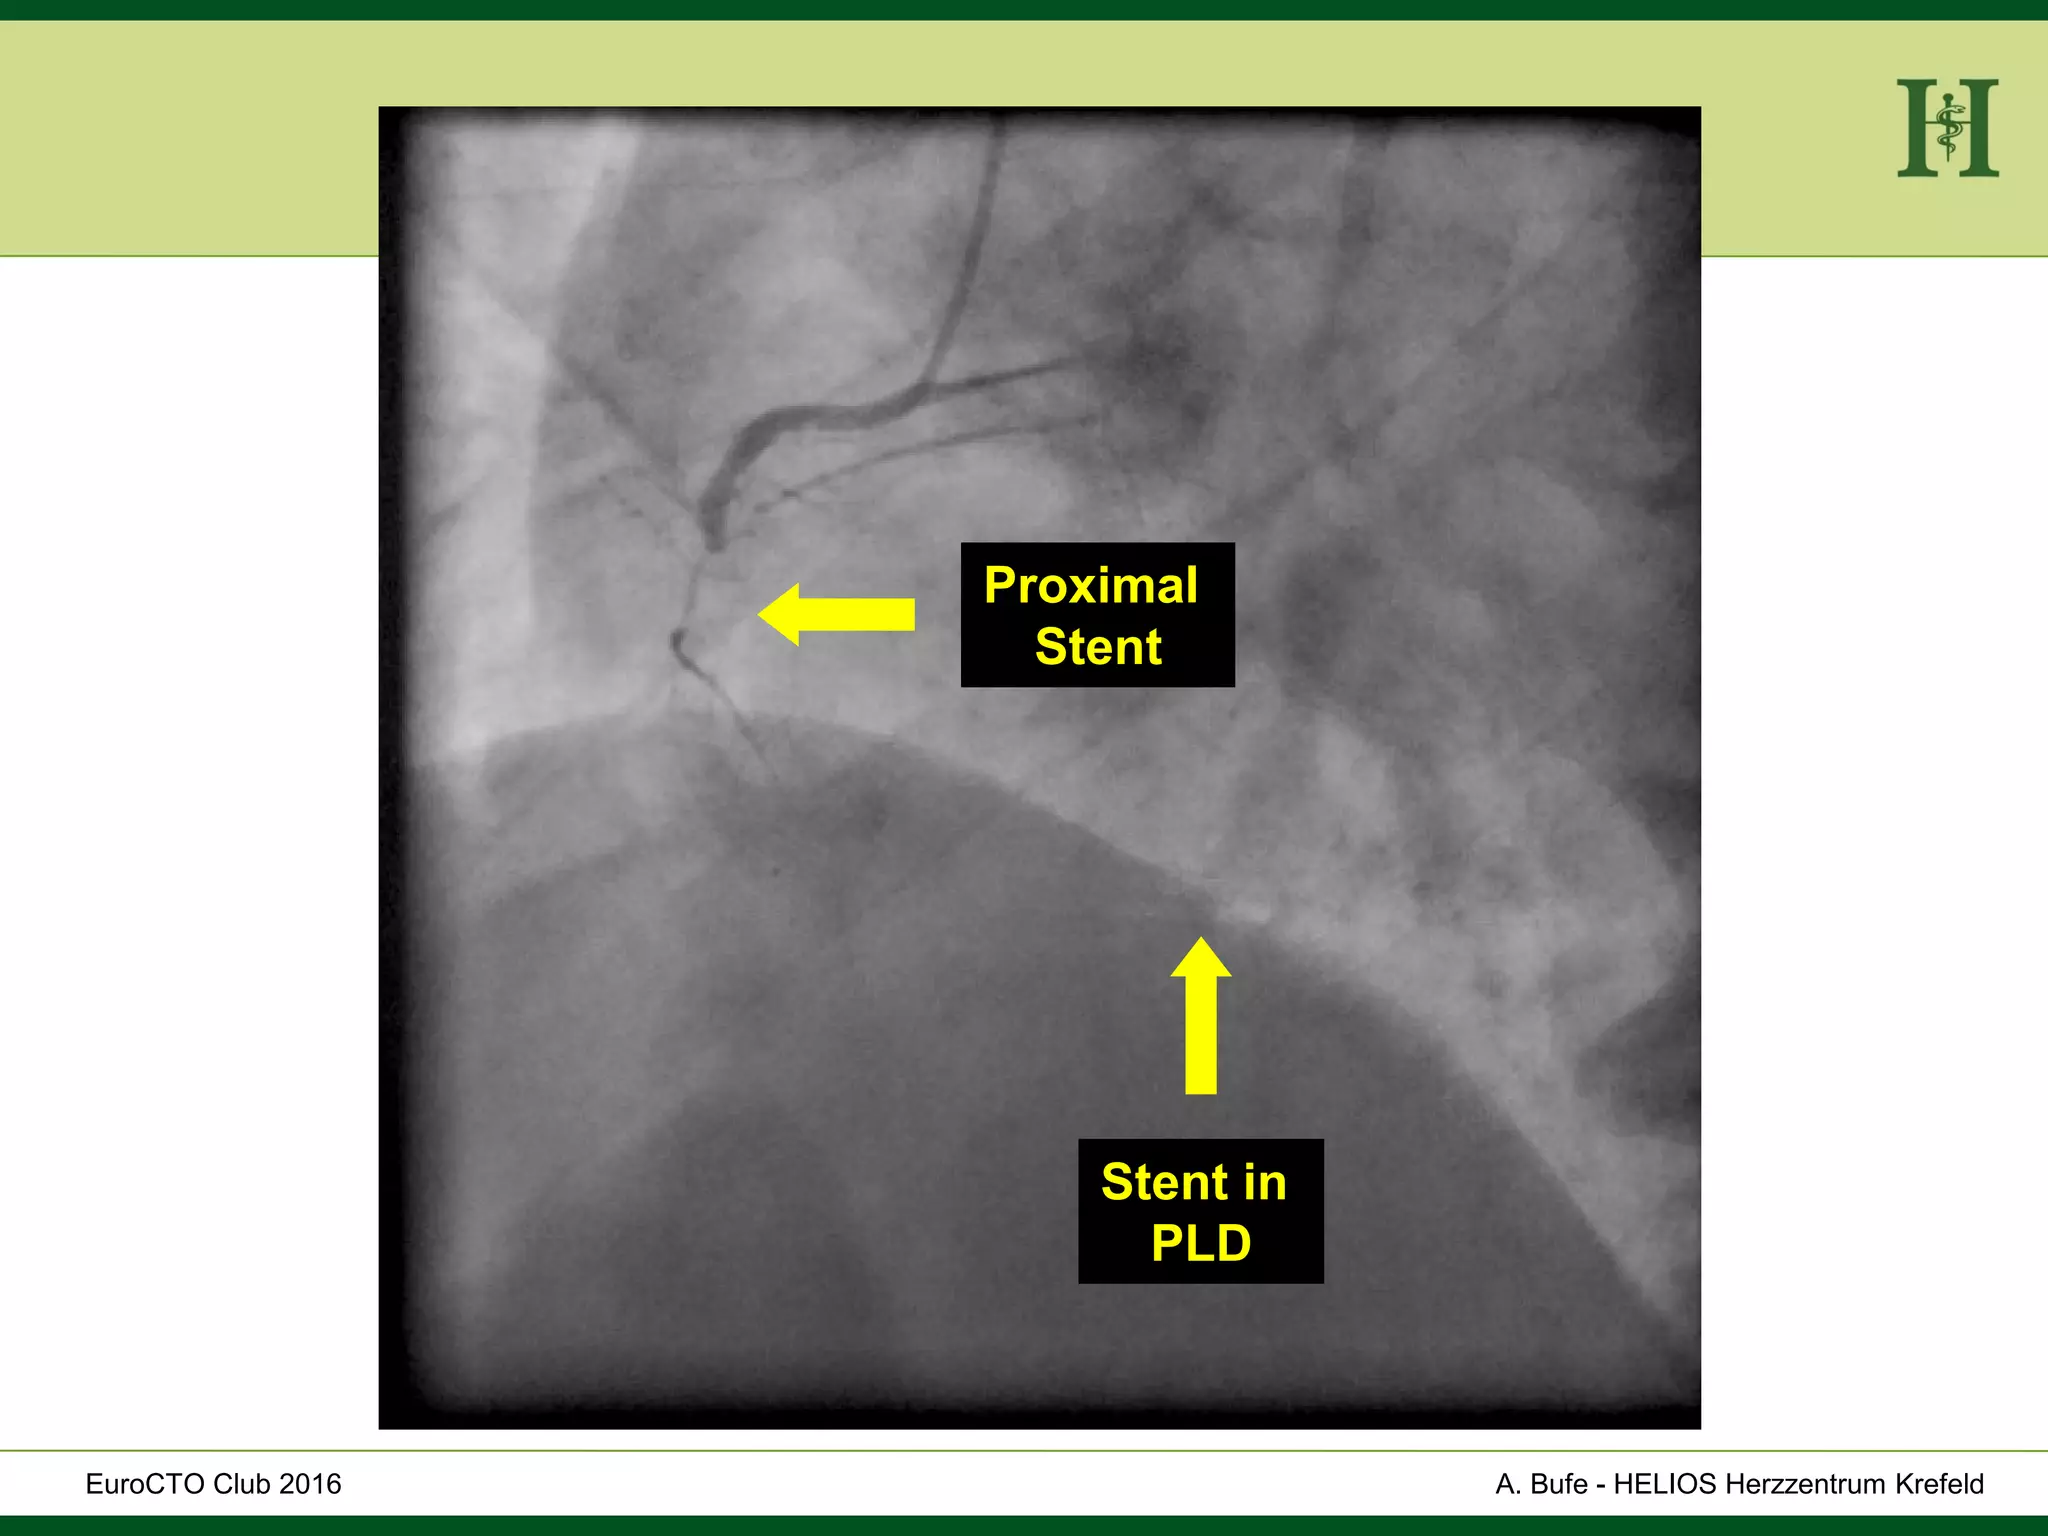

Proximal

Stent

Stent in

PLD

HELIOS Klinikum Wuppertal- HerzzentrumHELIOS Klinikum Wuppertal - Herzzentru A. Bufe - HELIOS Herzzentrum KrefeldEuroCTO Club 2016 Proximal Stent Stent in PLD